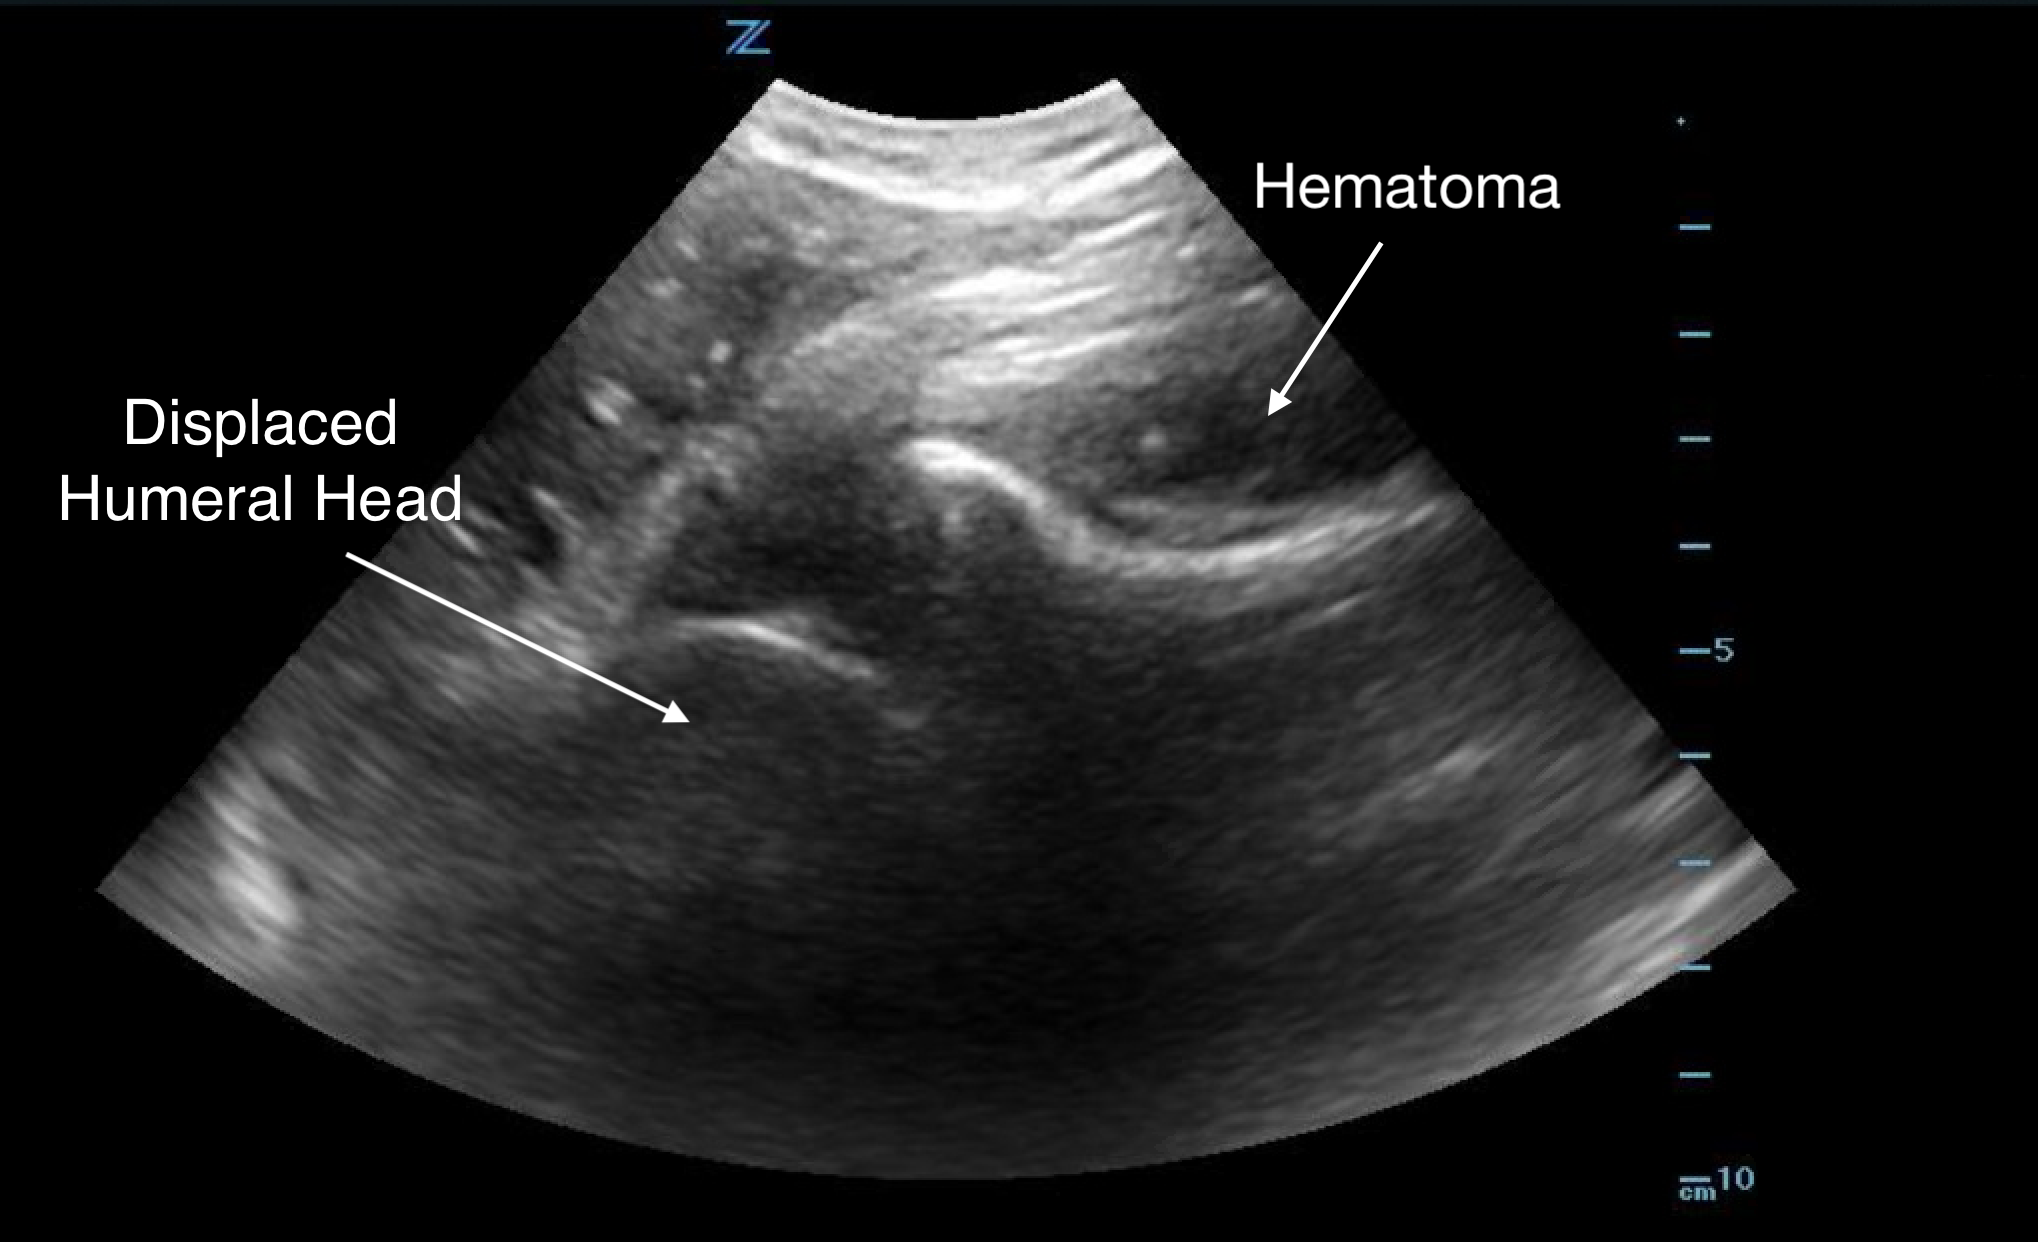

Shoulder Dislocation

Anterior Dislocation:

- The humeral head is displaced anterior to the glenoid.

- Appears at the bottom of the screen as the transducer is placed on the posterior shoulder.

- Movement is away from the transducer since the orientation is posterior-to-anterior.

Figure 9.

Anterior shoulder dislocation with overlying hematoma

Posterior Dislocation:

- The humeral head moves towards the transducer.

- Ultrasound is particularly helpful in diagnosing posterior dislocations, which can be difficult to identify on radiographs.

- If unclear, compare with the unaffected shoulder for clarity.

- Ultrasound is effective in confirming a successful reduction of the dislocation.

Note: Ultrasound should not replace radiographs; it is essential to determine the presence of underlying fractures both before and after reduction. Each imaging modality has its best applications, and they complement each other in patient evaluation and management.